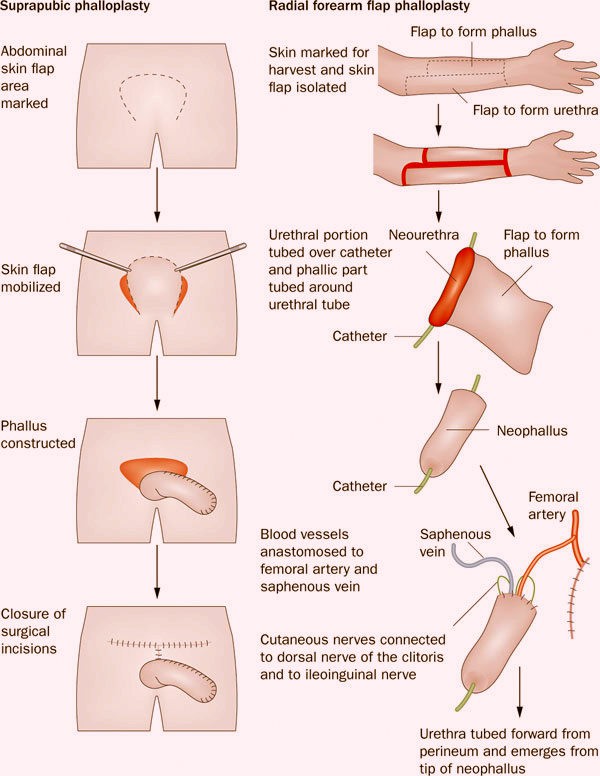

Phẫu thuật chuyển giới từ nữ sang nam, hay còn gọi là…